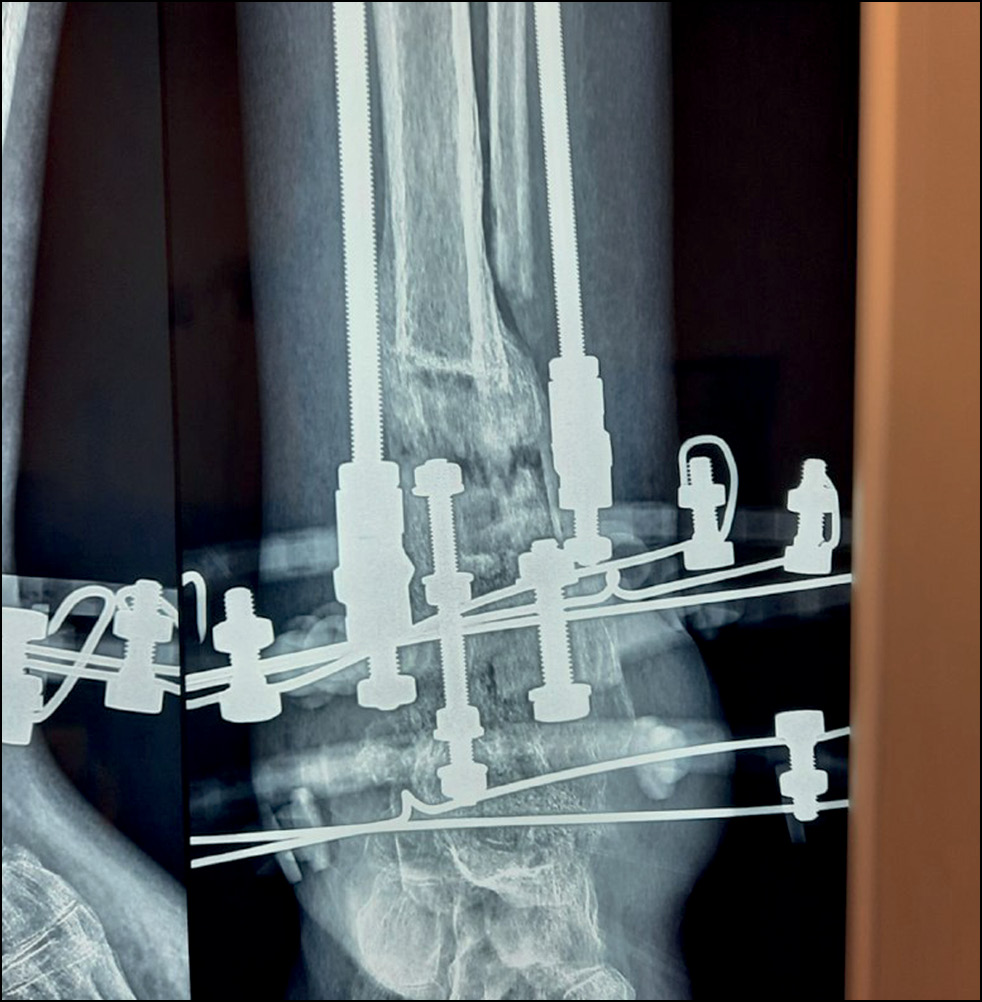

Под спинномозговой анестезией без кровоостанавливающего турникета наложен аппарат Илизарова на 4 модулях. Произведена остеотомия малоберцовой кости из наружного доступа 2,0 см и большеберцовой кости из доступа 4,0 см по передне-внутренней поверхности на высоте деформации в зоне имеющейся костной мозоли. Профилактика осложнений, перевязки операционных ран и режим нагрузки были идентичны проводимым ранее. Заживление ран первичное, осложнений в ближайшем послеоперационном периоде не наблюдалось.

Рис. 9. Рентгенограмма в передне-задней проекции после окончания коррекции варусной деформации.

Fig. 9. X-ray image in anterior-posterior projection after correction of varus deformity.

Через 10 дней после операции начата этапная дозированная дистракция в зоне остеотомии на переднезадних стержнях, соответствующих оси большеберцовой кости, 0,75 мм/сут, на медиальном стержне — 1,0 мм/сут. Каждые 2 недели проводилось рентгенографическое исследование для оценки степени коррекции деформации и контроля удлинения. После коррекции углового смещения (рис. 9) скорость дистракции на трёх стержнях была одинаковой — 0,75 мм/сут. Через 8 недель после начала дистракции, когда диастаз между костными фрагментами составлял 40 мм, была достигнута компенсация укорочения и деформации конечности, дистракция была остановлена. К этому времени отмечались начальные признаки формирования костного регенерата, рентгенологические признаки снижения МПКТ оставались на прежнем уровне. Маркеры костного метаболизма не выходили за пределы референса — остеокальцин 34,76 нг/мл (11–43), С-концевой телопептид коллагена I типа — 0,346 нг/мл (0,3–0,57). После коррекции дефицита витамина D (приём колекальциферола 50 000 МЕ еженедельно в течение 8 недель внутрь, далее 2000 МЕ ежедневно внутрь) уровень ПТГ нормализовался и составил 61,7 пг/мл (15–65).